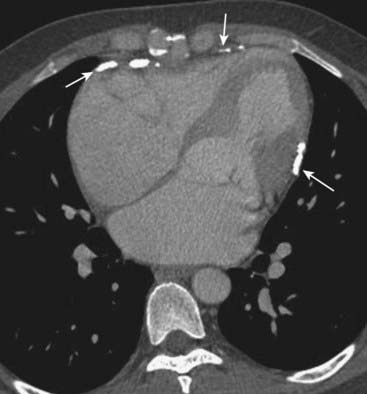

imageOn both MRI and CT, the diagnosis rests on identification of the intimal flap that separates the true (original) from the false lumen (canal created by the dissection) (Fig. 9-28).

image

Figure 9-28 Aortic dissections, types A and B.

A, An intimal flap is seen to traverse both the ascending (solid black arrow) and descending aorta (dotted black arrow). This is a Stanford type A dissection. B, There is a normal-appearing ascending aorta (dotted white arrow) while an intimal flap is noted by the black line traversing the descending aorta (solid black arrow). The intimal flap is the characteristic lesion of an aortic dissection. The smaller lumen is usually the true (original) lumen, and the larger, false lumen is actually a channel that has been produced by blood dissecting through the media.